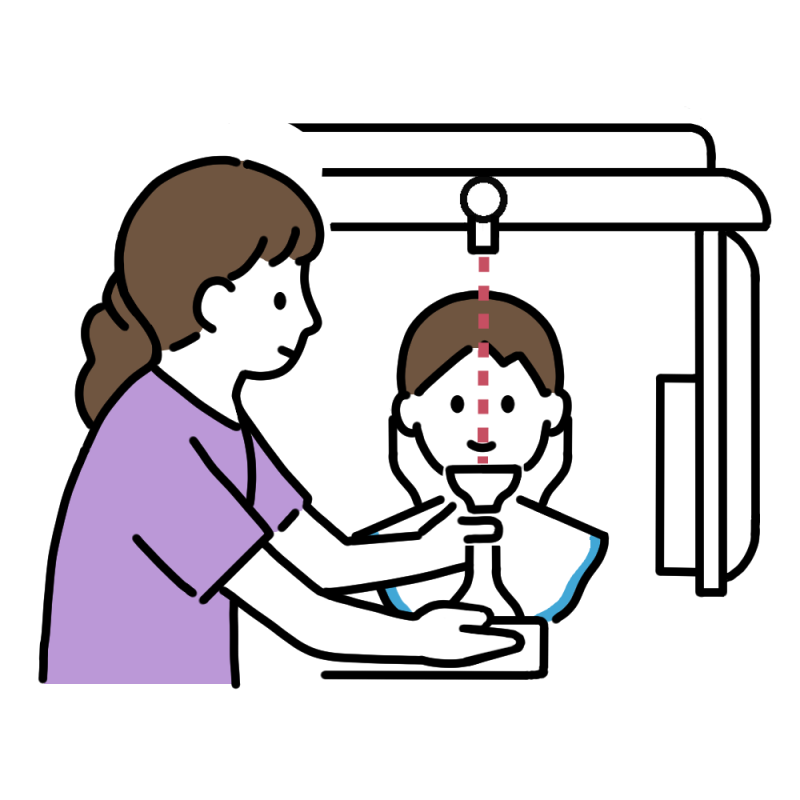

精密検査

カウンセリング後、矯正治療を始める前に必ず行うのが精密検査です。現在のお口の状態を把握し、今後の治療方針を決めるうえで非常に重要となります。

精密検査は主に4つの項目にわかれており、それぞれが適切な矯正治療を行うための診断に非常に重要な項目となります。詳しくは下記ブログをご覧ください。